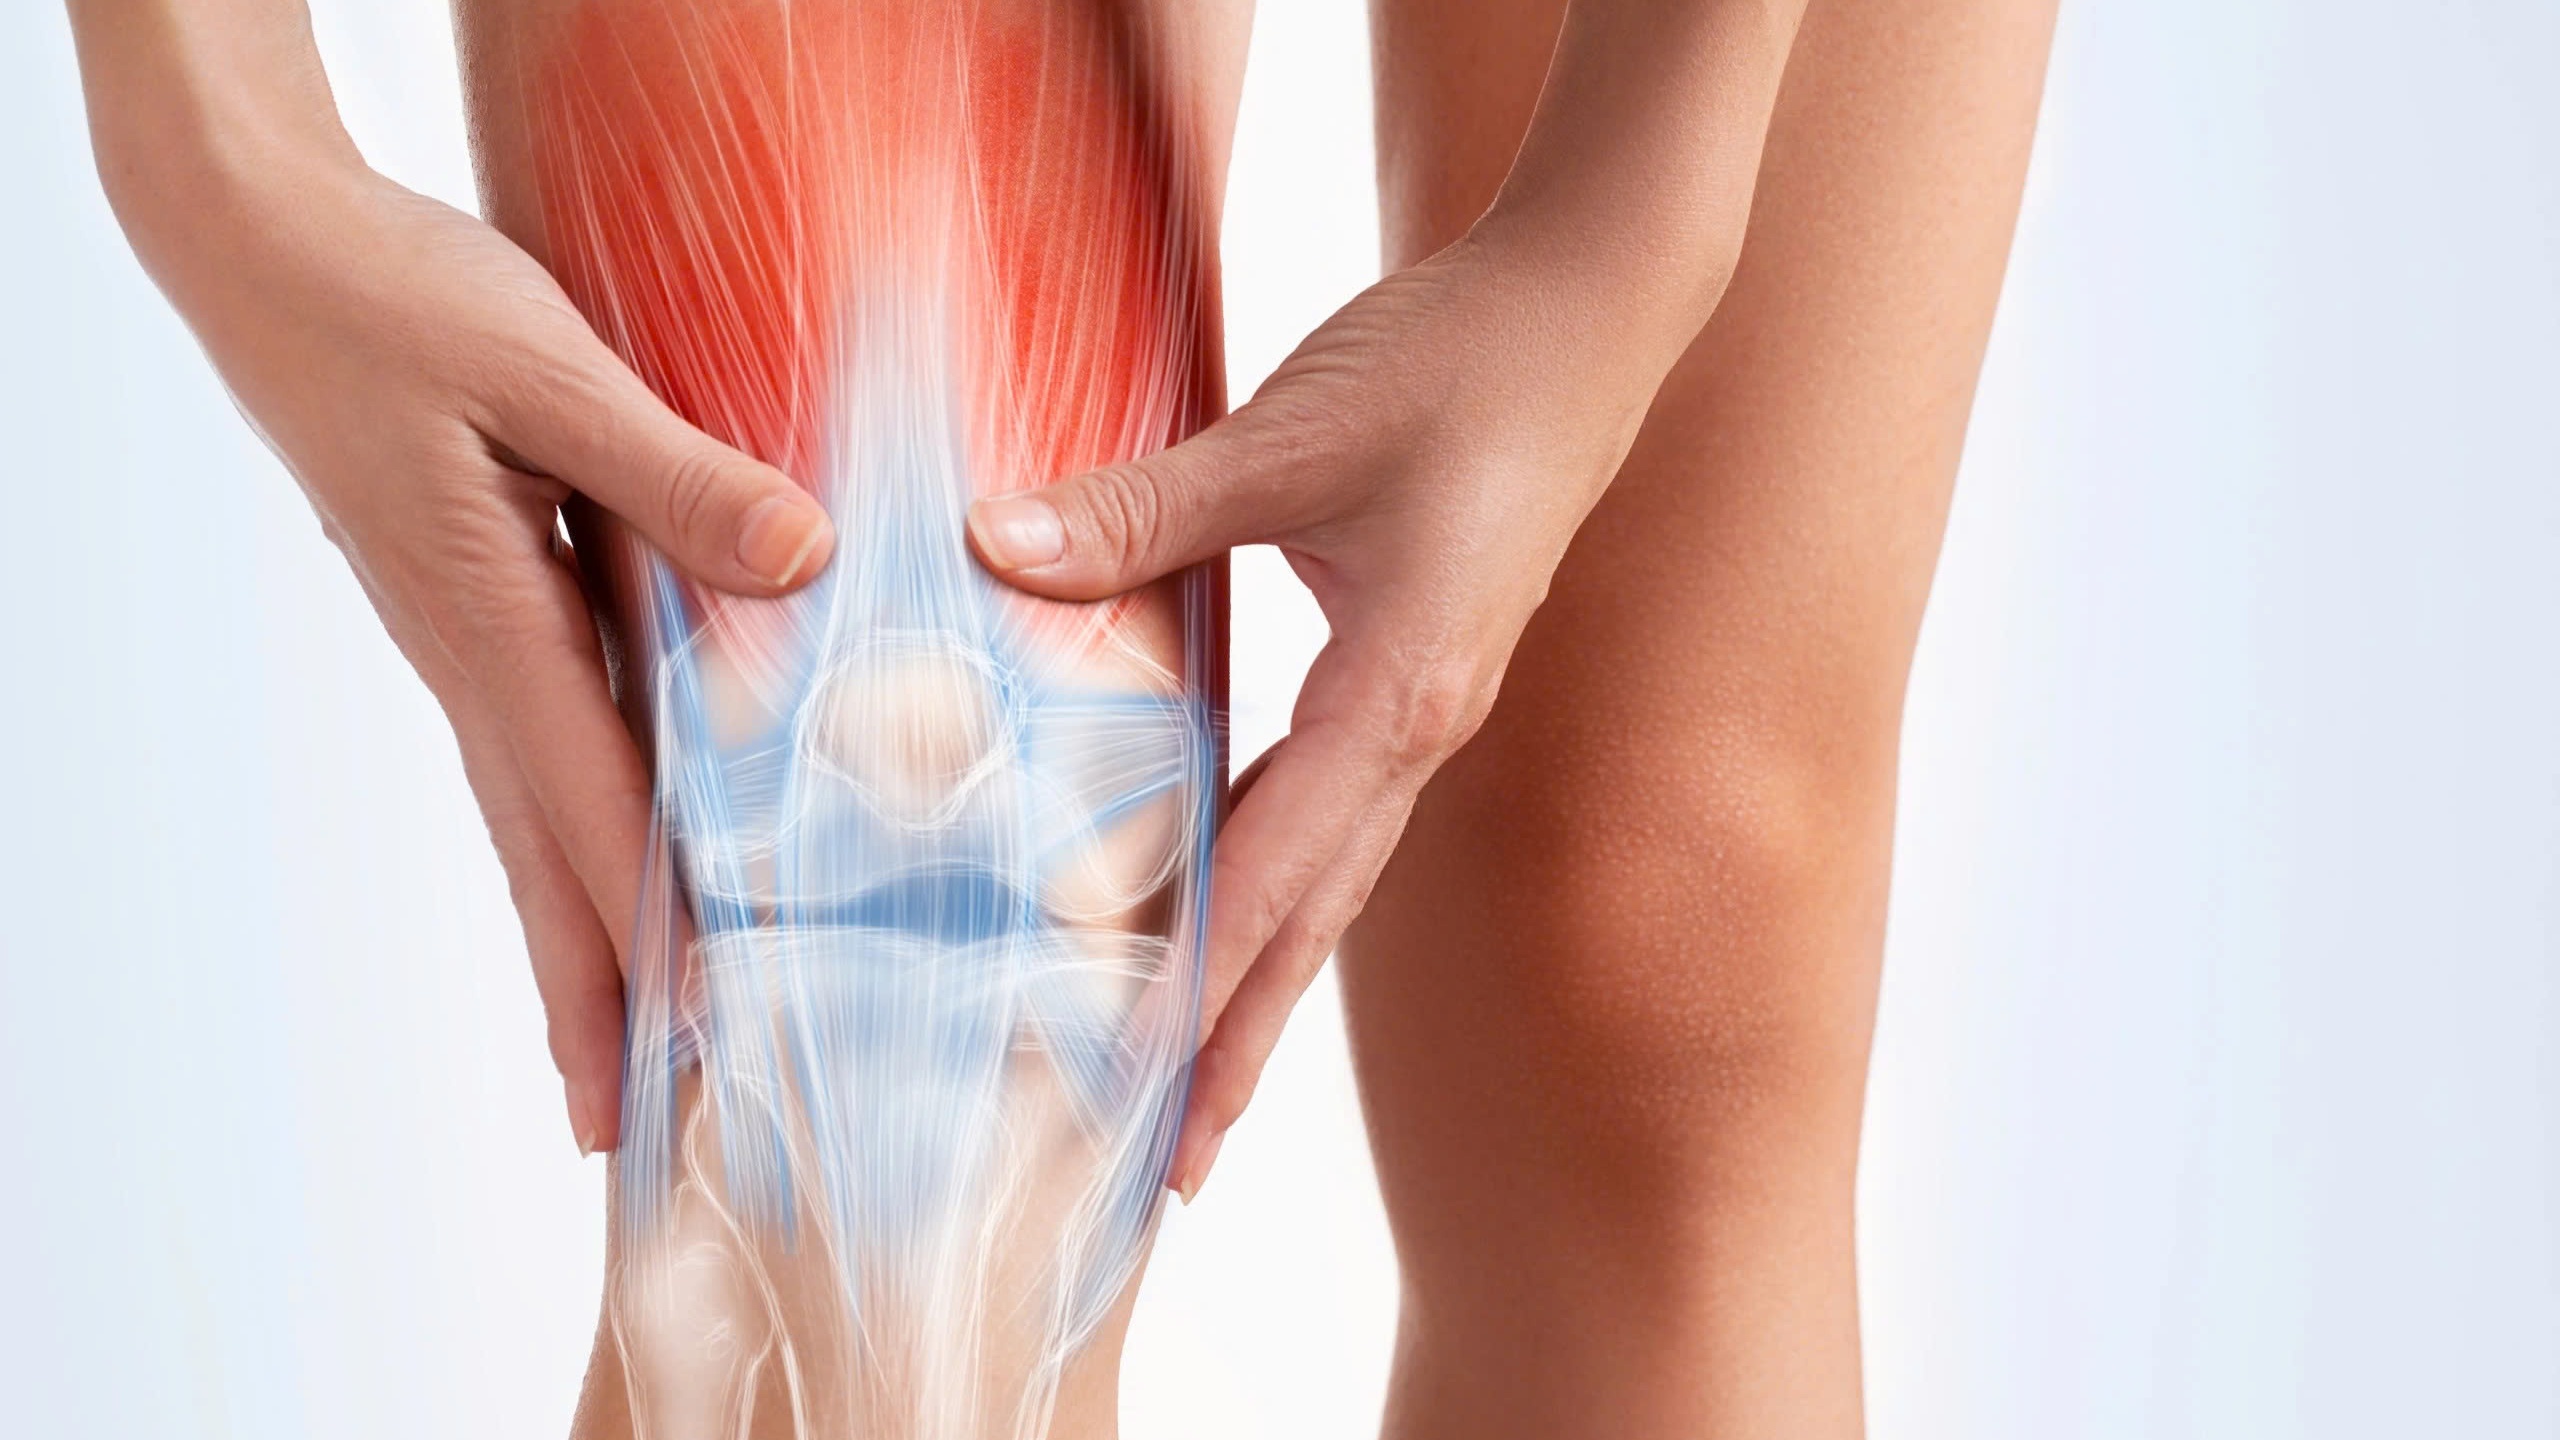

Thoái hóa khớp gối là một tình trạng thoái hóa trong đó lớp sụn bao bọc các đầu xương tại khớp gối bị mòn đi theo thời gian. Khớp gối là nơi gặp nhau của xương đùi và xương chày, cùng với xương bánh chè ở phía trước. Trong một khớp khỏe mạnh, các đầu xương được bao phủ bởi một lớp sụn trơn và mượt, giúp các xương di chuyển mà không có ma sát và bảo vệ khớp khỏi các tác động lực. Khi thoái hóa xảy ra, lớp sụn này bị mỏng đi, bề mặt trở nên thô ráp, dẫn đến đau và cứng khớp.

Thoái hóa khớp gối xảy ra khi có sự mất cân bằng giữa quá trình phá hủy và tái tạo sụn khớp. Các enzyme phá hủy sụn được tiết ra quá nhiều khiến sụn mất đi độ đàn hồi, nứt vỡ và dần dần bị bào mòn.